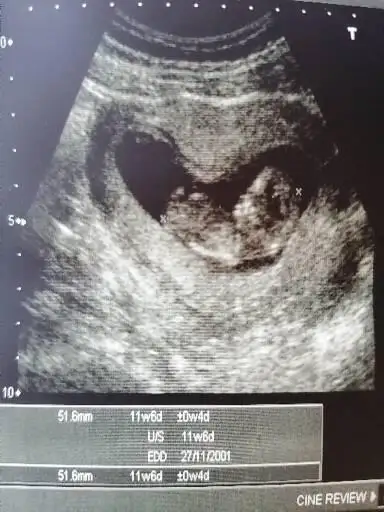

Bana da bakabilir misin ? 12+2

Bir tahmininiz var mı ?

• d3cfddcb-c882-47e7-b969-b16103955a25.webp

d3cfddcb-c882-47e7-b969-b16103955a25.webp

19,9 KB · Görüntüleme: 106